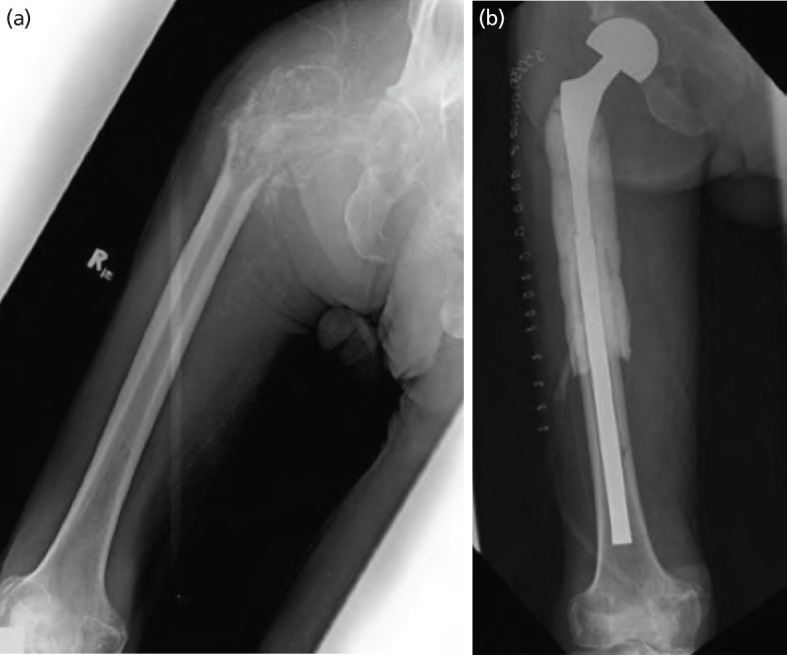

Introduction: The proximal femur is the most common long bone affected by metastatic disease. Pathologic fractures in this area are frequent, secondary to weight-bearing and deforming forces. Long-stem endoprosthetic replacement is often used to replace and bypass segments affected by metastases. However, implant cost remains prohibitive for patients in low-resource settings. An improvised megaprosthesis using a hip implant combined with Kuntscher nail provides an economic option.

Material and methods: This is a case series of three patients diagnosed with pathologic fracture of the hip secondary to metastatic bone disease who underwent proximal femoral resection with reconstruction using an improvised endoprosthesis in a single tertiary hospital. Outcomes determined include total blood loss, total surgical time, length of hospital stay, latest functional score using the Musculoskeletal Tumour Society (MSTS) score, and pain scale using the numerical rating scale (NRS).

Results: For case 1, a 42-year-old female with metastatic breast carcinoma, currently alive with disease and able to perform activities of daily living (ADLs) with minimal assistance; for case 2, a 77-year-old male diagnosed with prostatic carcinoma, able to ambulate with assistive device before expiring 2 years post-surgery; and for case 3, a 57-year-old female with metastatic breast carcinoma, able to resume unassisted ADLs at 3 months post-surgery before refusing systemic treatment in her second year of surveillance monitoring.